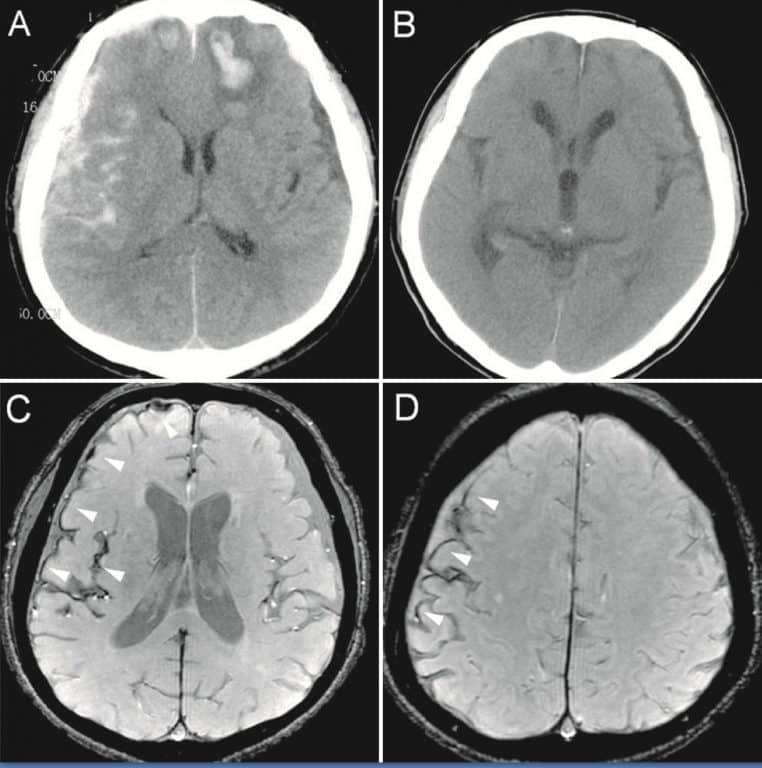

Micro-hémorragies : de petites traces sur l’IRM, un grand signal d’alarme

Les micro-hémorragies cérébrales sont de minuscules dépôts de sang visibles à l’IRM. La plupart du temps, elles ne déclenchent aucun symptôme immédiat. Elles n’en sont pas moins importantes : chez les personnes âgées, leur nombre augmente avec l’âge et s’associe à un risque majoré d’AVC et de déclin cognitif.

C’est là que l’étude de JAMA Network Open interpelle : chez les 1 441 participants atteints d’apnée du sommeil modérée à sévère, ces micro-saignements sont plus fréquents que chez des personnes sans apnée, et l’écart persiste même après avoir neutralisé statistiquement l’âge, le sexe, l’IMC, la tension artérielle, le diabète et les lipides.

En clair : les micro-coupures respiratoires de la nuit ne se contenteraient pas d’abréger le sommeil, elles laisseraient aussi des empreintes vasculaires dans le cerveau. Elles ne provoquent pas une démence à elles seules, mais elles installeraient un terrain moins favorable à la mémoire et à l’attention.

En apnée obstructive, les voies aériennes se referment et l’oxygène sanguin chute. Ces hypoxies intermittentes, répétées nuit après nuit, déclenchent des réponses inflammatoires et vasculaires. Sur le cerveau, elles se traduisent par un stress oxydatif, des atteintes de la paroi des petits vaisseaux et, au fil du temps, par des micro-hémorragies visibles en imagerie.